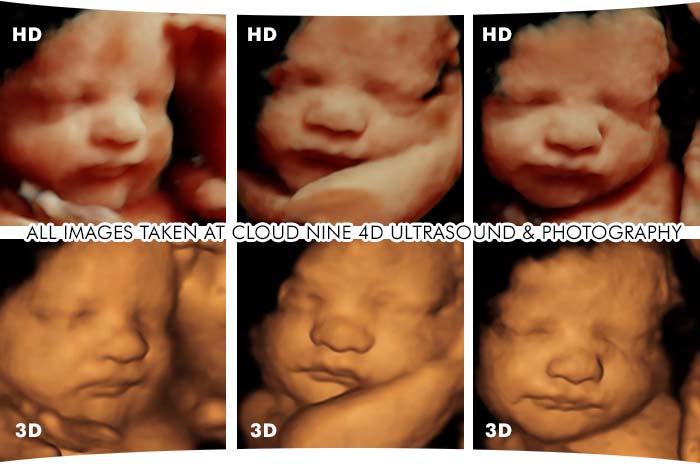

Los ultrasonidos 4D son una forma avanzada de realizar una ecografía, que permite obtener imágenes en tiempo real del feto. A diferencia de las ecografías tradicionales que solo producen imágenes en 2D, los ultrasonidos 4D ofrecen imágenes en 3D y 4D, que permiten una mayor claridad y detalle. Esto significa que los médicos y padres pueden ver las características físicas y el comportamiento del feto, lo que ayuda a detectar cualquier problema de salud o desarrollo en una etapa temprana.

3D ultrasound / 4D Ultrasound / HD Ultrasound - Chattanooga, TNEs importante destacar que los ultrasonidos 4D deben ser realizados por profesionales capacitados y en clínicas de confianza para garantizar su seguridad y efectividad. La FDA recomienda realizar solo dos o tres ultrasonidos durante el embarazo, ya que los ultrasonidos pueden generar calor y producir efectos biológicos en el feto. Por lo tanto, es importante seguir las recomendaciones del médico y solo realizar los ultrasonidos que sean necesarios.